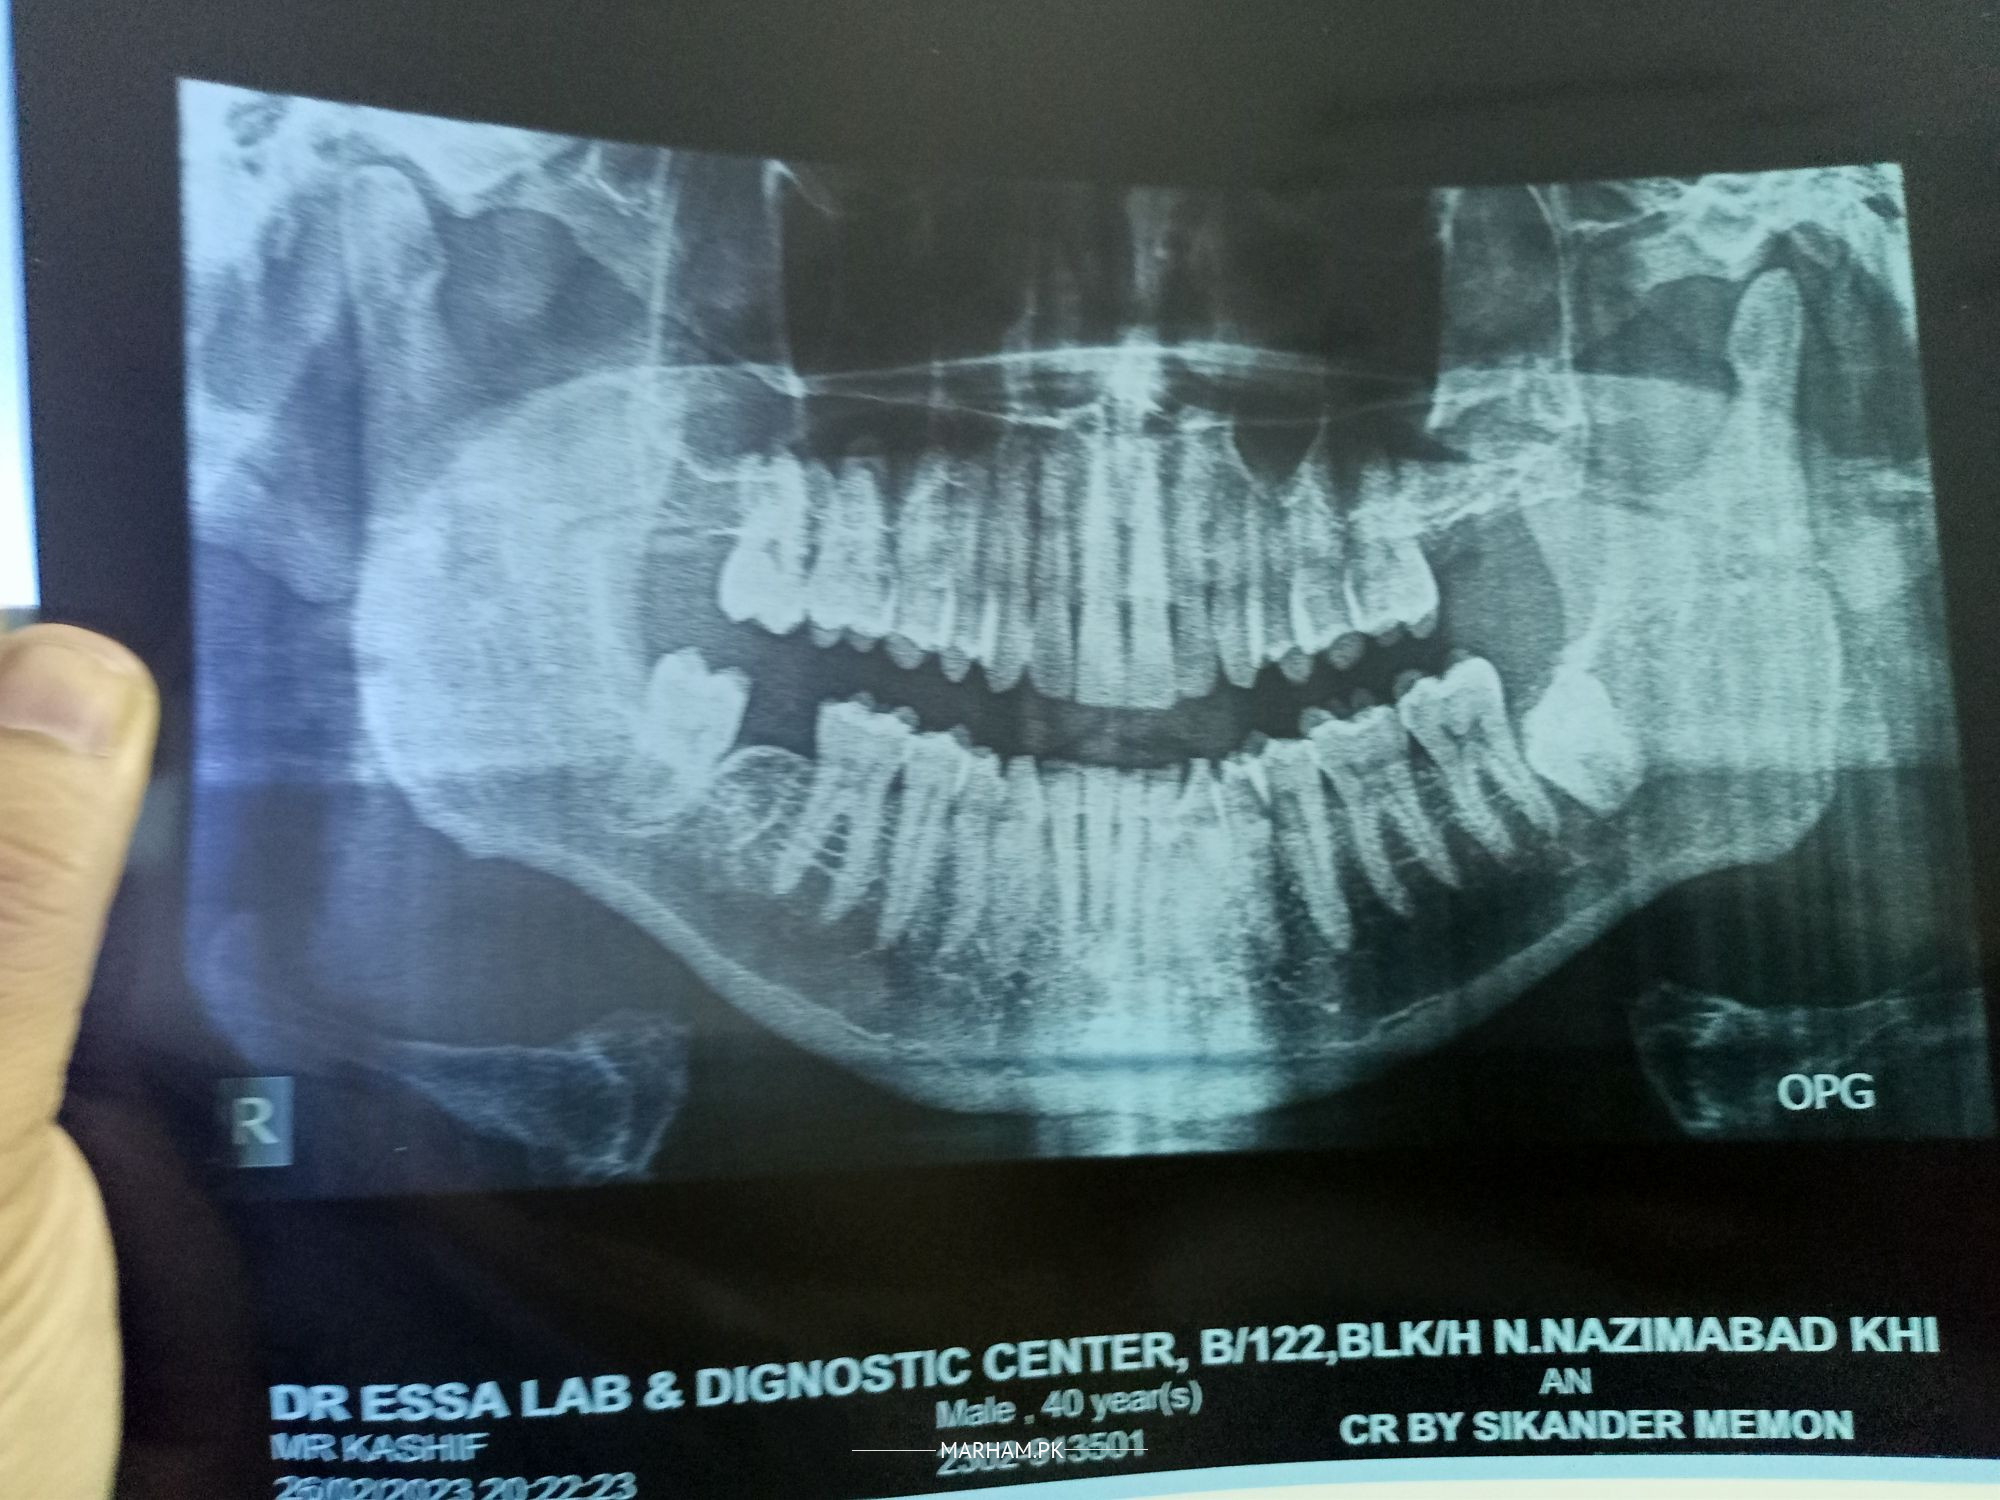

recommend lowest fee for right wisdom teeth extraction

Wisdom tooth extraction is complicated may be done manual and surgically depending on the case.

Here lower left wisdom extraction will be surgical.

Charges vary between 6000 to 10000